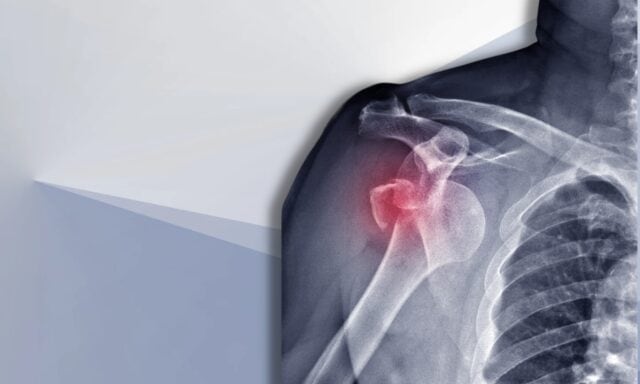

V tejto epizóde budeme hovoriť o všetkých veciach týkajúcich sa nestability ramien. Dozviete sa viac o Stanmorovej klasifikácii a štrukturálnych poškodeniach po vykĺbení. Rozoberieme si typického pacienta s nestabilitou ramena a ako vyzerá proces vyšetrenia. Dotkneme sa vzorcov svalovej aktivácie, chirurgického zákroku a toho, ako by mohol vyzerať fyzioterapeutický manažment pacienta s nestabilitou ramena. Takže si určite vypočujte celú epizódu!